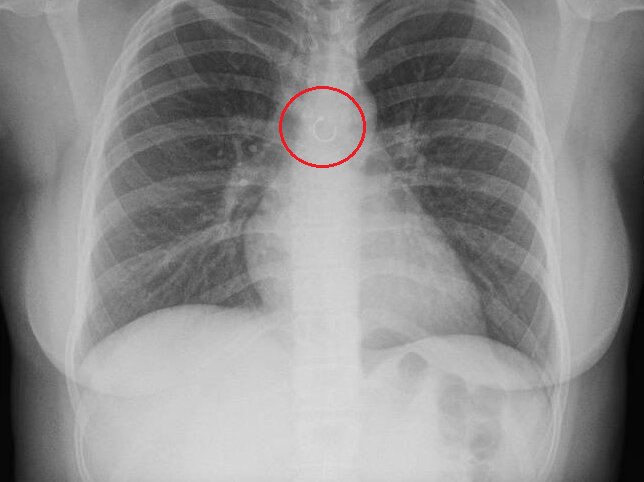

Ten najprv pripisovala zmene počasia. Bežné vysvetlenie, ktoré by napadlo asi každému. Lenže kašeľ neustupoval a postupne sa zhoršoval. Až návšteva lekára odhalila šokujúcu pravdu – jej stratený piercing sa nenachádzal nikde inde než v pľúcach. Lekári zistili, že malý kovový krúžok sa dostal do dýchacích ciest pravdepodobne počas spánku, keď ho nevedomky vdýchla. Situácia bola o to vážnejšia, že predmet sa nachádzal len približne pol milimetra od aorty, jednej z najdôležitejších tepien v tele.

Prvá operácia trvala viac ako hodinu, no lekárom sa nepodarilo piercing odstrániť. Bol totiž prichytený k tkanivu pľúc, čo zákrok výrazne skomplikovalo. Až druhý pokus bol úspešný. Najdesivejším momentom však zostáva fakt, že ak by sa krúžok posunul o zlomok milimetra, mohol poškodiť aortu. To by pravdepodobne viedlo k okamžitému kolapsu pľúc alebo fatálnemu krvácaniu.